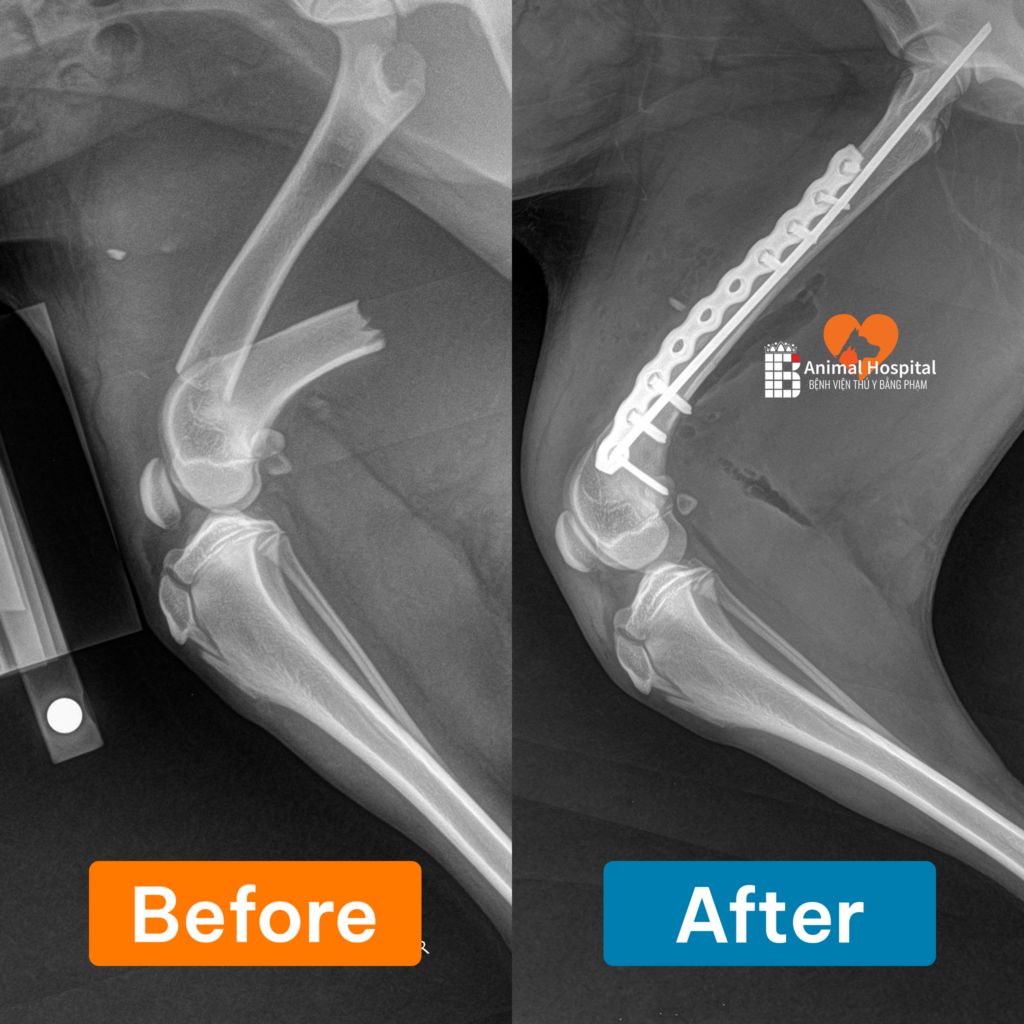

2.1. Khảo sát hệ xương khớp và chấn thương

Đây là ứng dụng phổ biến nhất của Máy X Quang Kỹ Thuật Số VR120. Hình ảnh có độ tương phản cao giúp bác sĩ dễ dàng xác định các tình trạng như: gãy xương, rạn nứt xương do tai nạn, trật khớp, bẩm sinh thoái hóa khớp (như loạn sản khớp háng) hoặc các tổn thương bất thường ở cột sống.